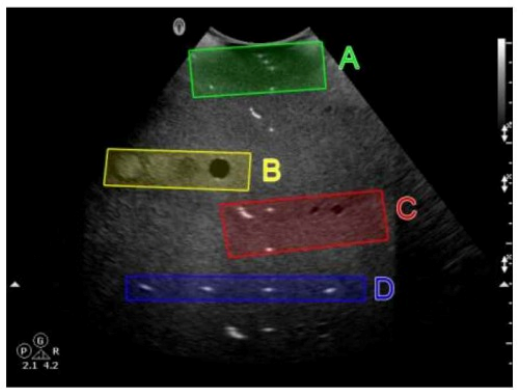

Which target group is used to evaluate transverse distance measurement accuracy in this tissue-mimicking phantom image?

Answer : C

In a tissue-mimicking phantom, the group of targets aligned side-by-side (horizontally) is used to evaluate transverse (lateral) distance measurement accuracy. In the image, target group C (in red) represents the lateral spacing targets.

Group A (top) is typically for near field assessment.

Group B may be for axial resolution or cyst evaluation.

Group D (deep) may assess depth calibration or sensitivity.

Therefore, the correct answer is C: C.